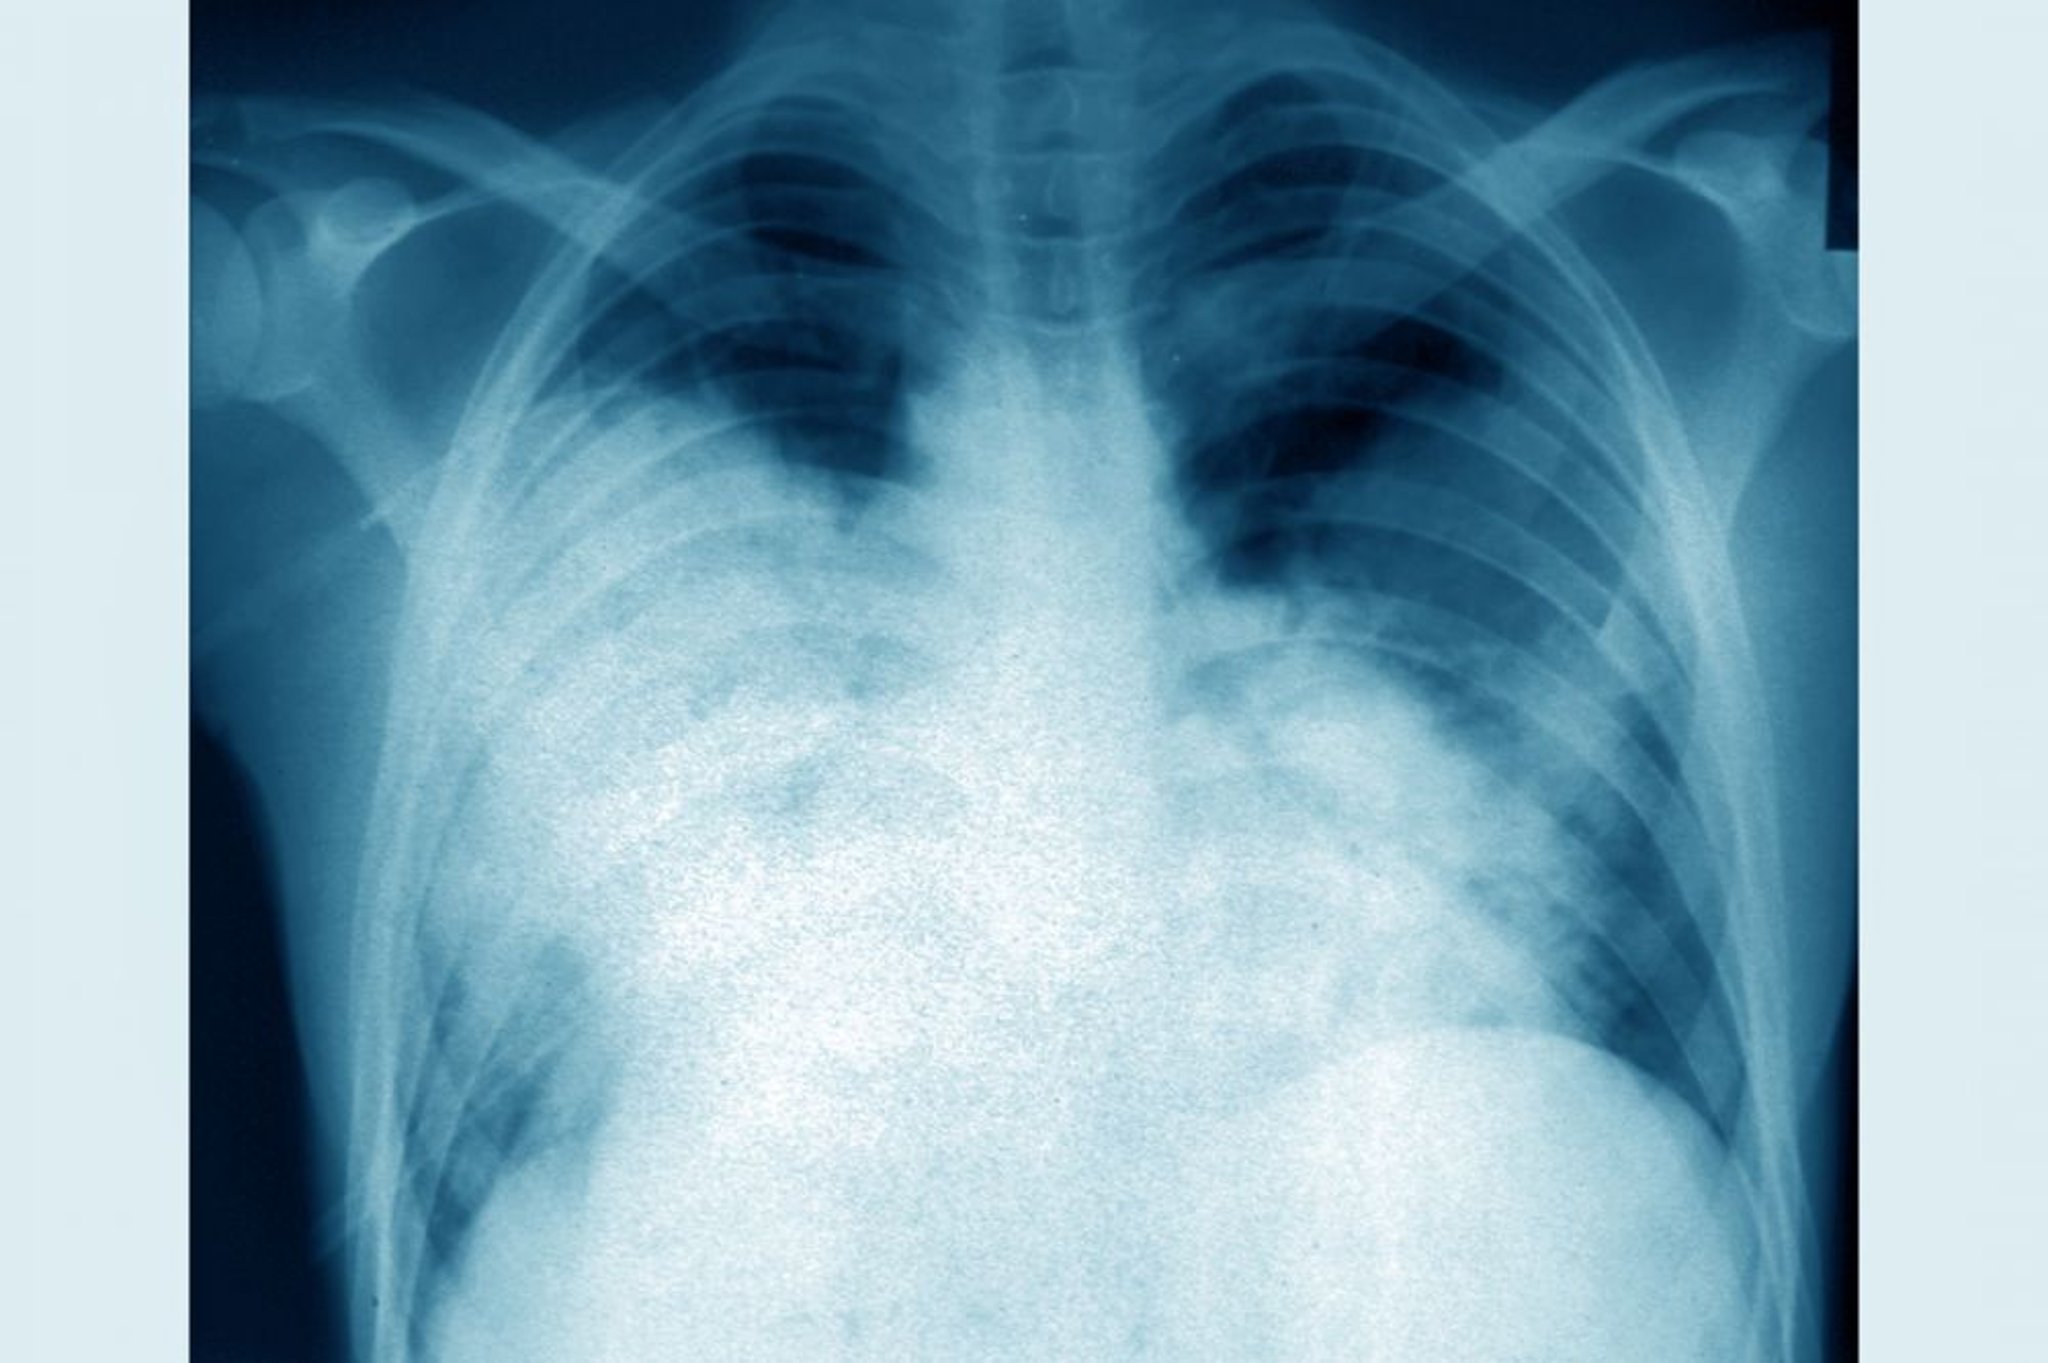

Необхідно провести рентгенологічне дослідження органів грудної клітки. Зазвичай воно виявляє плями та швидко асиметрично прогресуючі інфільтрати (навіть на фоні ефективної антибіотикотерапії) з невеликим плевральним випотом або без нього.